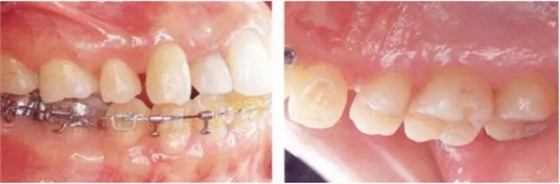

▲圖19-5,6

▲圖19-5 初期治療完成后的狀態(tài),炎癥得到了很好的控制。

▲圖19-6 在下頜右側磨牙部植入種植體恢復垂直高度以及形成支抗點,開始正畸治療。

▲圖19-7

正畸治療完成時。